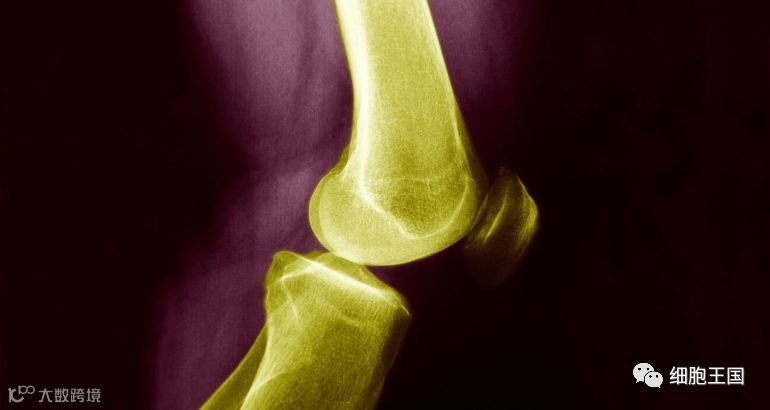

骨关节炎是一种退行性病变,由于关节软骨退化损伤和破坏等引起,在60岁以上的人群中患病率可达50%,75岁以上的人群中则达80%,致残率高达53%,是近年来中老年致残率最高的疾病之一。随着现代人们肥胖、不恰当运动及遗传等因素的影响,骨关节炎的发病人群越来越呈现年轻化的趋势。

骨关节炎的临床表现为缓慢发展的关节疼痛、压痛、僵硬、关节肿胀、活动受限和关节畸形等。早期常表现为负重、下蹲、上楼或下楼时膝关节疼痛。该病目前只有三种传统治疗方式,包括药物治疗、物理治疗及手术治疗对骨关节炎的治疗效果均不理想,这促使医药企业和临床医生努力去寻找新的治疗方法。